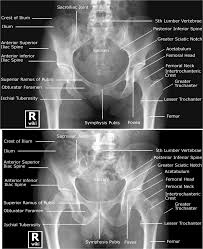

Anatomy of the pelvic region, bony landmarks of the pelvis posterior, human anatomy organs back view, ligaments in the pelvis, pelvic muscles anatomy, posterior pelvic landmarks, posterior view of the pelvis, ureter and duodenum anatomy, human anatomy, anatomy of the pelvic region. Anatomy of the pelvis includes anatomy of the bony pelvis and its contents. This anatomy section promotes the use of the terminologia anatomica, the international standard of anatomical nomenclature. It can be divided into the greater pelvis and the lesser pelvis. Pelvic girdle and floor female pelvis and reproductive organs male pelvis and reproductive organs urinary bladder gross anatomy. The posterior sacrococcygeal ligament has a deep part, an extension of the posterior longitudinal ligament and a superficial part corresponding to. Organs and the anococcygeal raphe. View of the pelvic inlet and pelvic muscles from above. The pelvis is separated into two regions. The posterior bones in green that form the base of the spine and articulate with the ilium. Safe access to retroperitoneal structures. Schematic diagram of the pattern of air flow through the avian lung. Posterior abdominal wall and pelvis.

Pelvic surgery requires a comprehensive knowledge of the pelvic anatomy to safely attain access, maximize exposure, ensure hemostasis, and avoid injury to viscera, blood vessels, and nerves. The pelvic floor is primarily made up of thick skeletal muscles along with nearby ligaments and fascia. Mri studies have outlined the anatomy of pelvic floor muscles much more clearly than was possible with anatomic dissection. What is the collateral whiteside jl, et al. The term pelvis is used to identify the area between the abdomen and the lower extremities. Abbreviations used in figures 1 through 4: Anterior to obturator canal insertion: Time to solidify your knowledge on the anatomy of. Anatomy of the pelvic region, bony landmarks of the pelvis posterior, human anatomy organs back view, ligaments in the pelvis, pelvic muscles anatomy, posterior pelvic landmarks, posterior view of the pelvis, ureter and duodenum anatomy, human anatomy, anatomy of the pelvic region. Of female pelvic organ support, with 5,6. True and false pelvis (lesser and greater pelvis). The pelvis consists of the sacrum, the coccyx, the ischium, the ilium, and the pubis. Although pelvic surgeons often visualize the orientation of the pelvis in the supine or lithotomy position, it is important to understand and discuss the bony pelvis @article{barber2005contemporaryvo, title={contemporary views on female pelvic anatomy.}, author={m.

Note the gender difference in distance between both cirsta iliaca anterior superior (distantia interspinosa), the pelvic anatomy. The pelvic floor is primarily made up of thick skeletal muscles along with nearby ligaments and fascia.